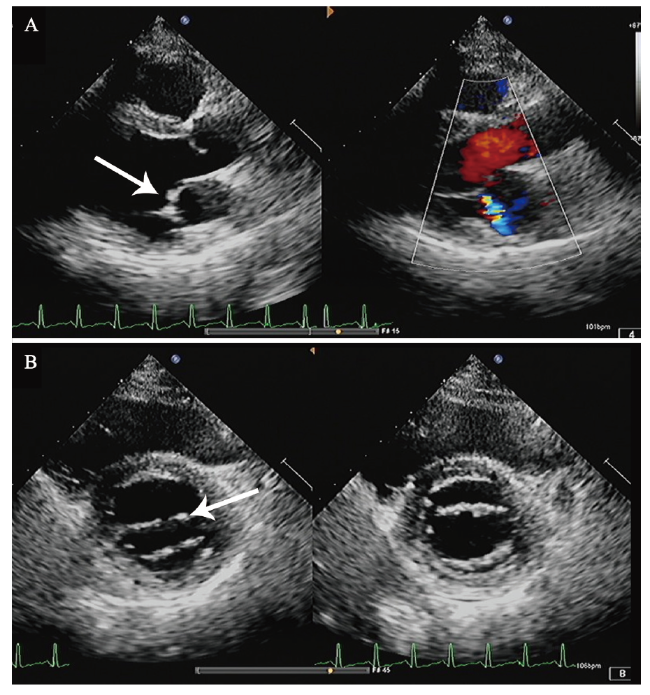

血常规示白细胞、红细胞、血红蛋白、血小板大致正常,ESR 115 mm/h,CRP 46.63 mg/L,D-二聚体7.04 mg/L,抗ds-DNA抗体阳性(++),抗核抗体 977 kU/L,抗β2糖蛋白Ⅰ抗体IgG 97.7 kU/L,抗心磷脂抗体IgM 2.3 MPLU/ml。CD4+/CD8+ T淋巴细胞3.00,狼疮样抗凝物(+)。Ig及补体正常。心电图:窦性心动过速,轻度ST段压低,T波低平(Ⅱ,Ⅲ,aVF,V1 ~ V6导联)。双下肢动静脉彩色多普勒超声示未见明确血栓征象。于2019年8月9日完善UCG检查,结果提示二尖瓣前叶赘生物形成?感染性心内膜炎不能完全除外,见图1A。完善抗“O”试验阴性,多次血培养均未见异常。

图1 一例SLE继发APS合并Libman -Sacks心内膜炎患者的UCG结果

A:左心室长轴切面示二尖瓣前叶赘生物形成(箭头示);B:二尖瓣水平短轴切面示二尖瓣瓣尖局限性增厚(箭头示)

入院后患者未再出现发热,考虑感染性心内膜炎不能完全除外,于8月11日加用头孢曲松钠抗感染。于8月12日复查UCG,结果示二尖瓣瓣尖局限性增厚。结合患者病史,考虑Libman-Sacks心内膜炎可能,见图1。予以甲泼尼龙治疗,起始剂量为80 mg/d口服,逐渐减量,7 d后减至40 mg/d口服,并予低分子肝素抗凝,加用环磷酰胺0.4 g,每2周1次,同时予营养神经、抑酸护胃治疗。8月20日,患者出现发热,最高体温为38.3℃,下肢搔抓处皮肤破损分泌物病原学培养出嗜麦芽窄食单胞菌,考虑患者发热与此相关,根据药物敏感试验结果改用左氧氟沙星联合复方磺胺甲口恶唑抗感染,之后体温降至正常。8月27日患者午休期间突发头晕、口周麻木、构音不清、吞咽困难,查头颅MRI见一新发的延髓梗死灶。结合患者临床表现、体征及辅助检查,主要诊断为:APS,Libman-Sacks心内膜炎,延髓梗死,SLE。继续予甲泼尼龙40 mg/d抑制免疫、羟氯喹调节免疫,加用环磷酰胺0.4 g (累积量为1.2 g)、低分子肝素抗凝,同时抗血小板聚集、营养神经、抑酸护胃治疗,定期监测国际标准化比值(INR),调整华法林剂量,复查血常规、肝肾功能未见明显异常,凝血酶原时间29.1 s,INR 2.80,无出血表现,患者病情好转,于9月30日出院。出院后门诊随访,一般情况可,至撰稿日无特殊不适。